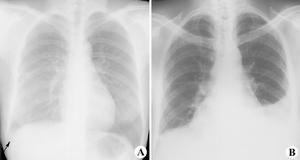

1、X 線胸片 少量積液可僅表現為患側肋膈角模糊、變鈍或消失;中等量積液可見患側下胸部大片均勻的緻密陰影,上緣呈外高內低的弧形;大量積液時患側胸部呈大片均勻的緻密陰影,氣管和縱隔對側移位,患側膈肌下移;包裹性積液表現為大小不等的圓形或半圓形均勻的緻密陰影,邊緣光滑清晰;葉間積液在側位片上呈長軸與葉間裂一致的邊緣銳利的梭狀均勻的緻密陰影;肺底積液在正位片上易與膈肌升高混淆,患側臥位透視或拍片則可見膈肌水平正常,胸水沿下側胸壁分布。X 線檢查不僅可以診斷積液,而且有助於原發病的診斷。

2、結核性胸膜炎 治療原則為全身抗結核藥物治療加上胸腔穿刺抽液。抽液宜分次進行,儘量抽盡胸液,殘留積液易導致胸膜肥厚粘連或形成包裹性積液。關於皮質激素的使用問題素有爭論,多數學者主張治療1 周后仍有發熱者應加用潑尼松,5~10mg,3 次/d,退熱後即減量,總療程為1個月。胸腔局部一般不宜注射抗結核藥,它可能促使形成包裹性積液。